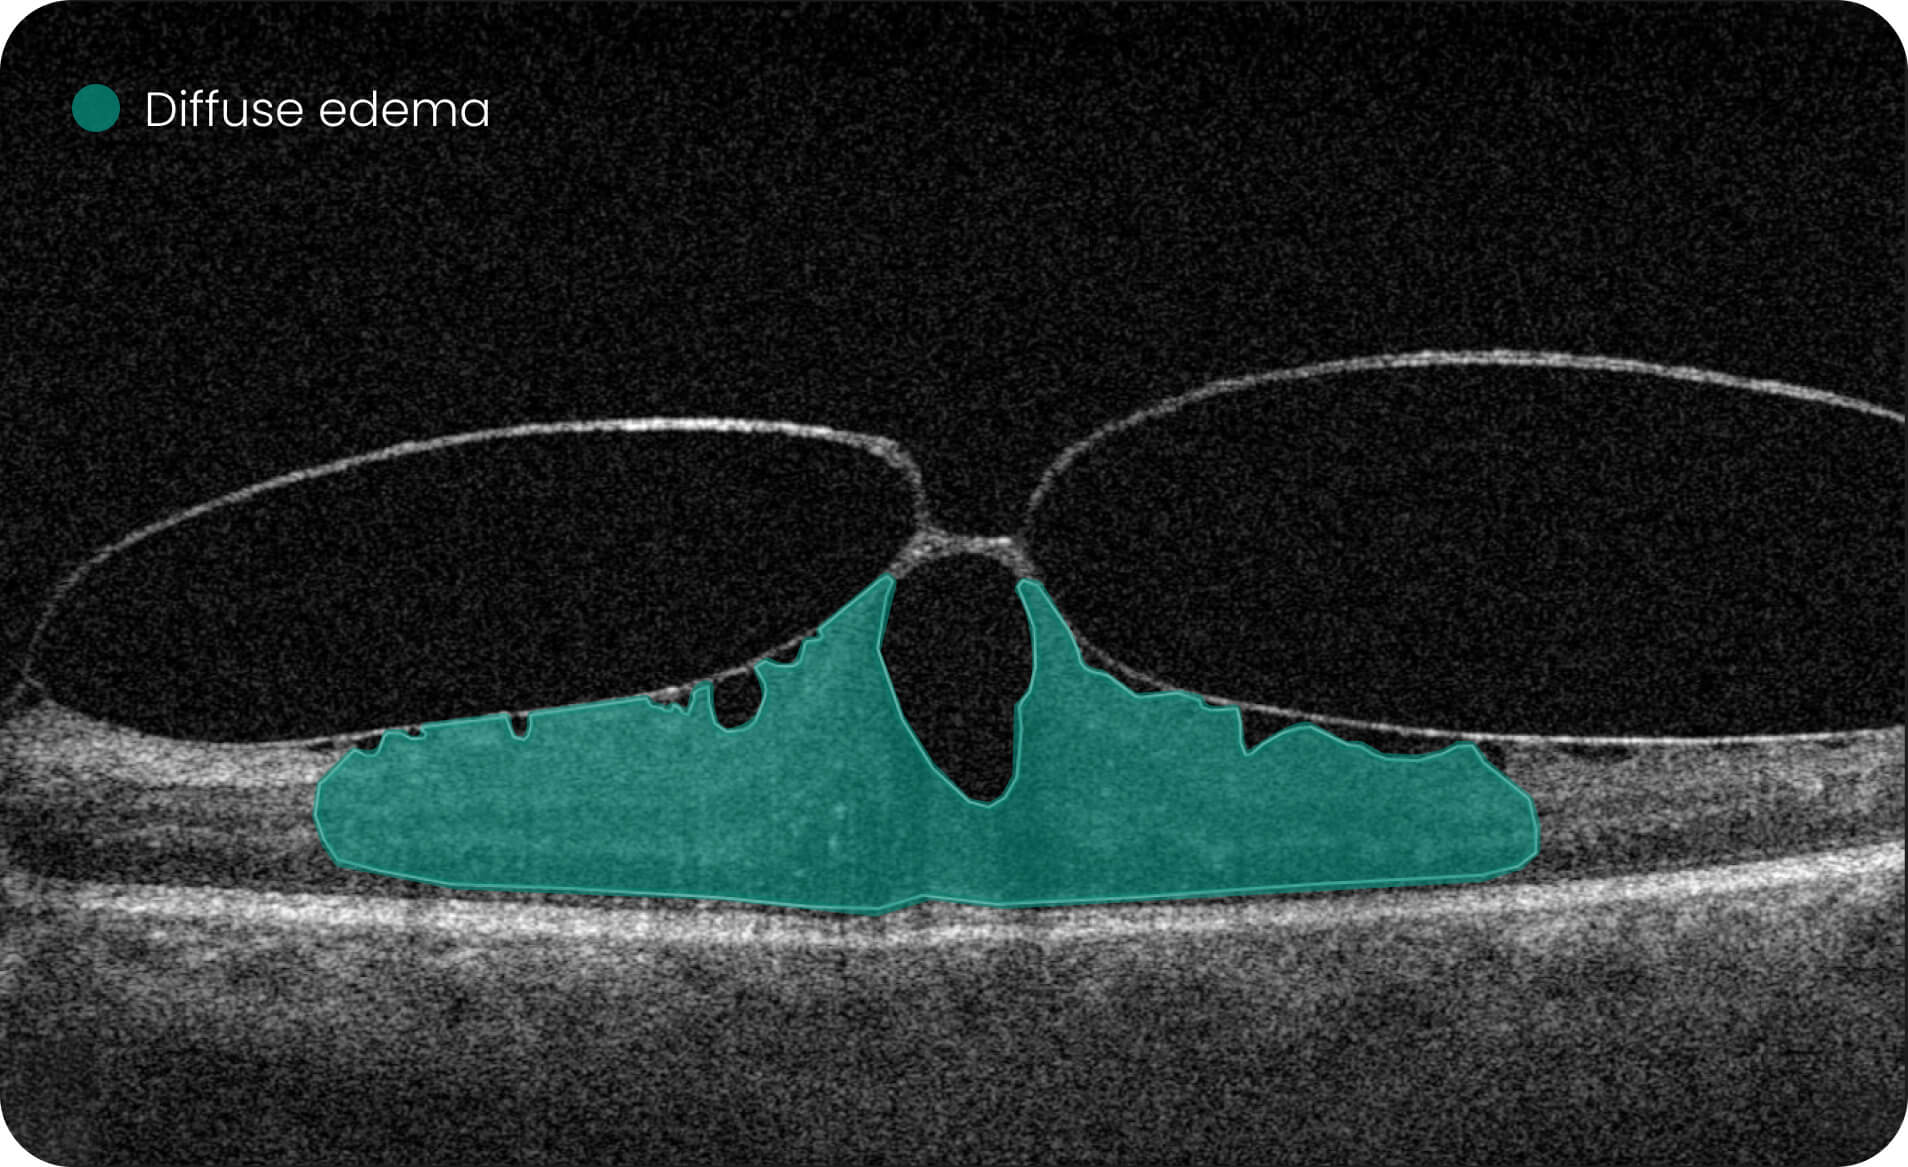

Characterization and visualization of OCT features commonly studied in Geographic Atrophy (GA), including hypertransmission, RPE atrophy, neurosensory retinal atrophy, and EZ changes.

The GA Progression feature provides tools for research-oriented visualization and comparison of OCT imaging data across multiple visits. Users can review changes in areas associated with geographic atrophy (GA) and related imaging features through percentage-based displays, maps, and graphs.

Efficient estimations of GA-associated areas designed to support research-focused image review workflows.

Quantitative, image-derived measurements of GA-related features and associated biomarkers for research analyses.

- 40+retinal biomarkers studied in research across 30+ retinal conditions. For Research Use Only. Not for diagnostic procedures.

- Quantitative exploration of 40+ biomarkers for Research Use Only. Not for diagnostic procedures.